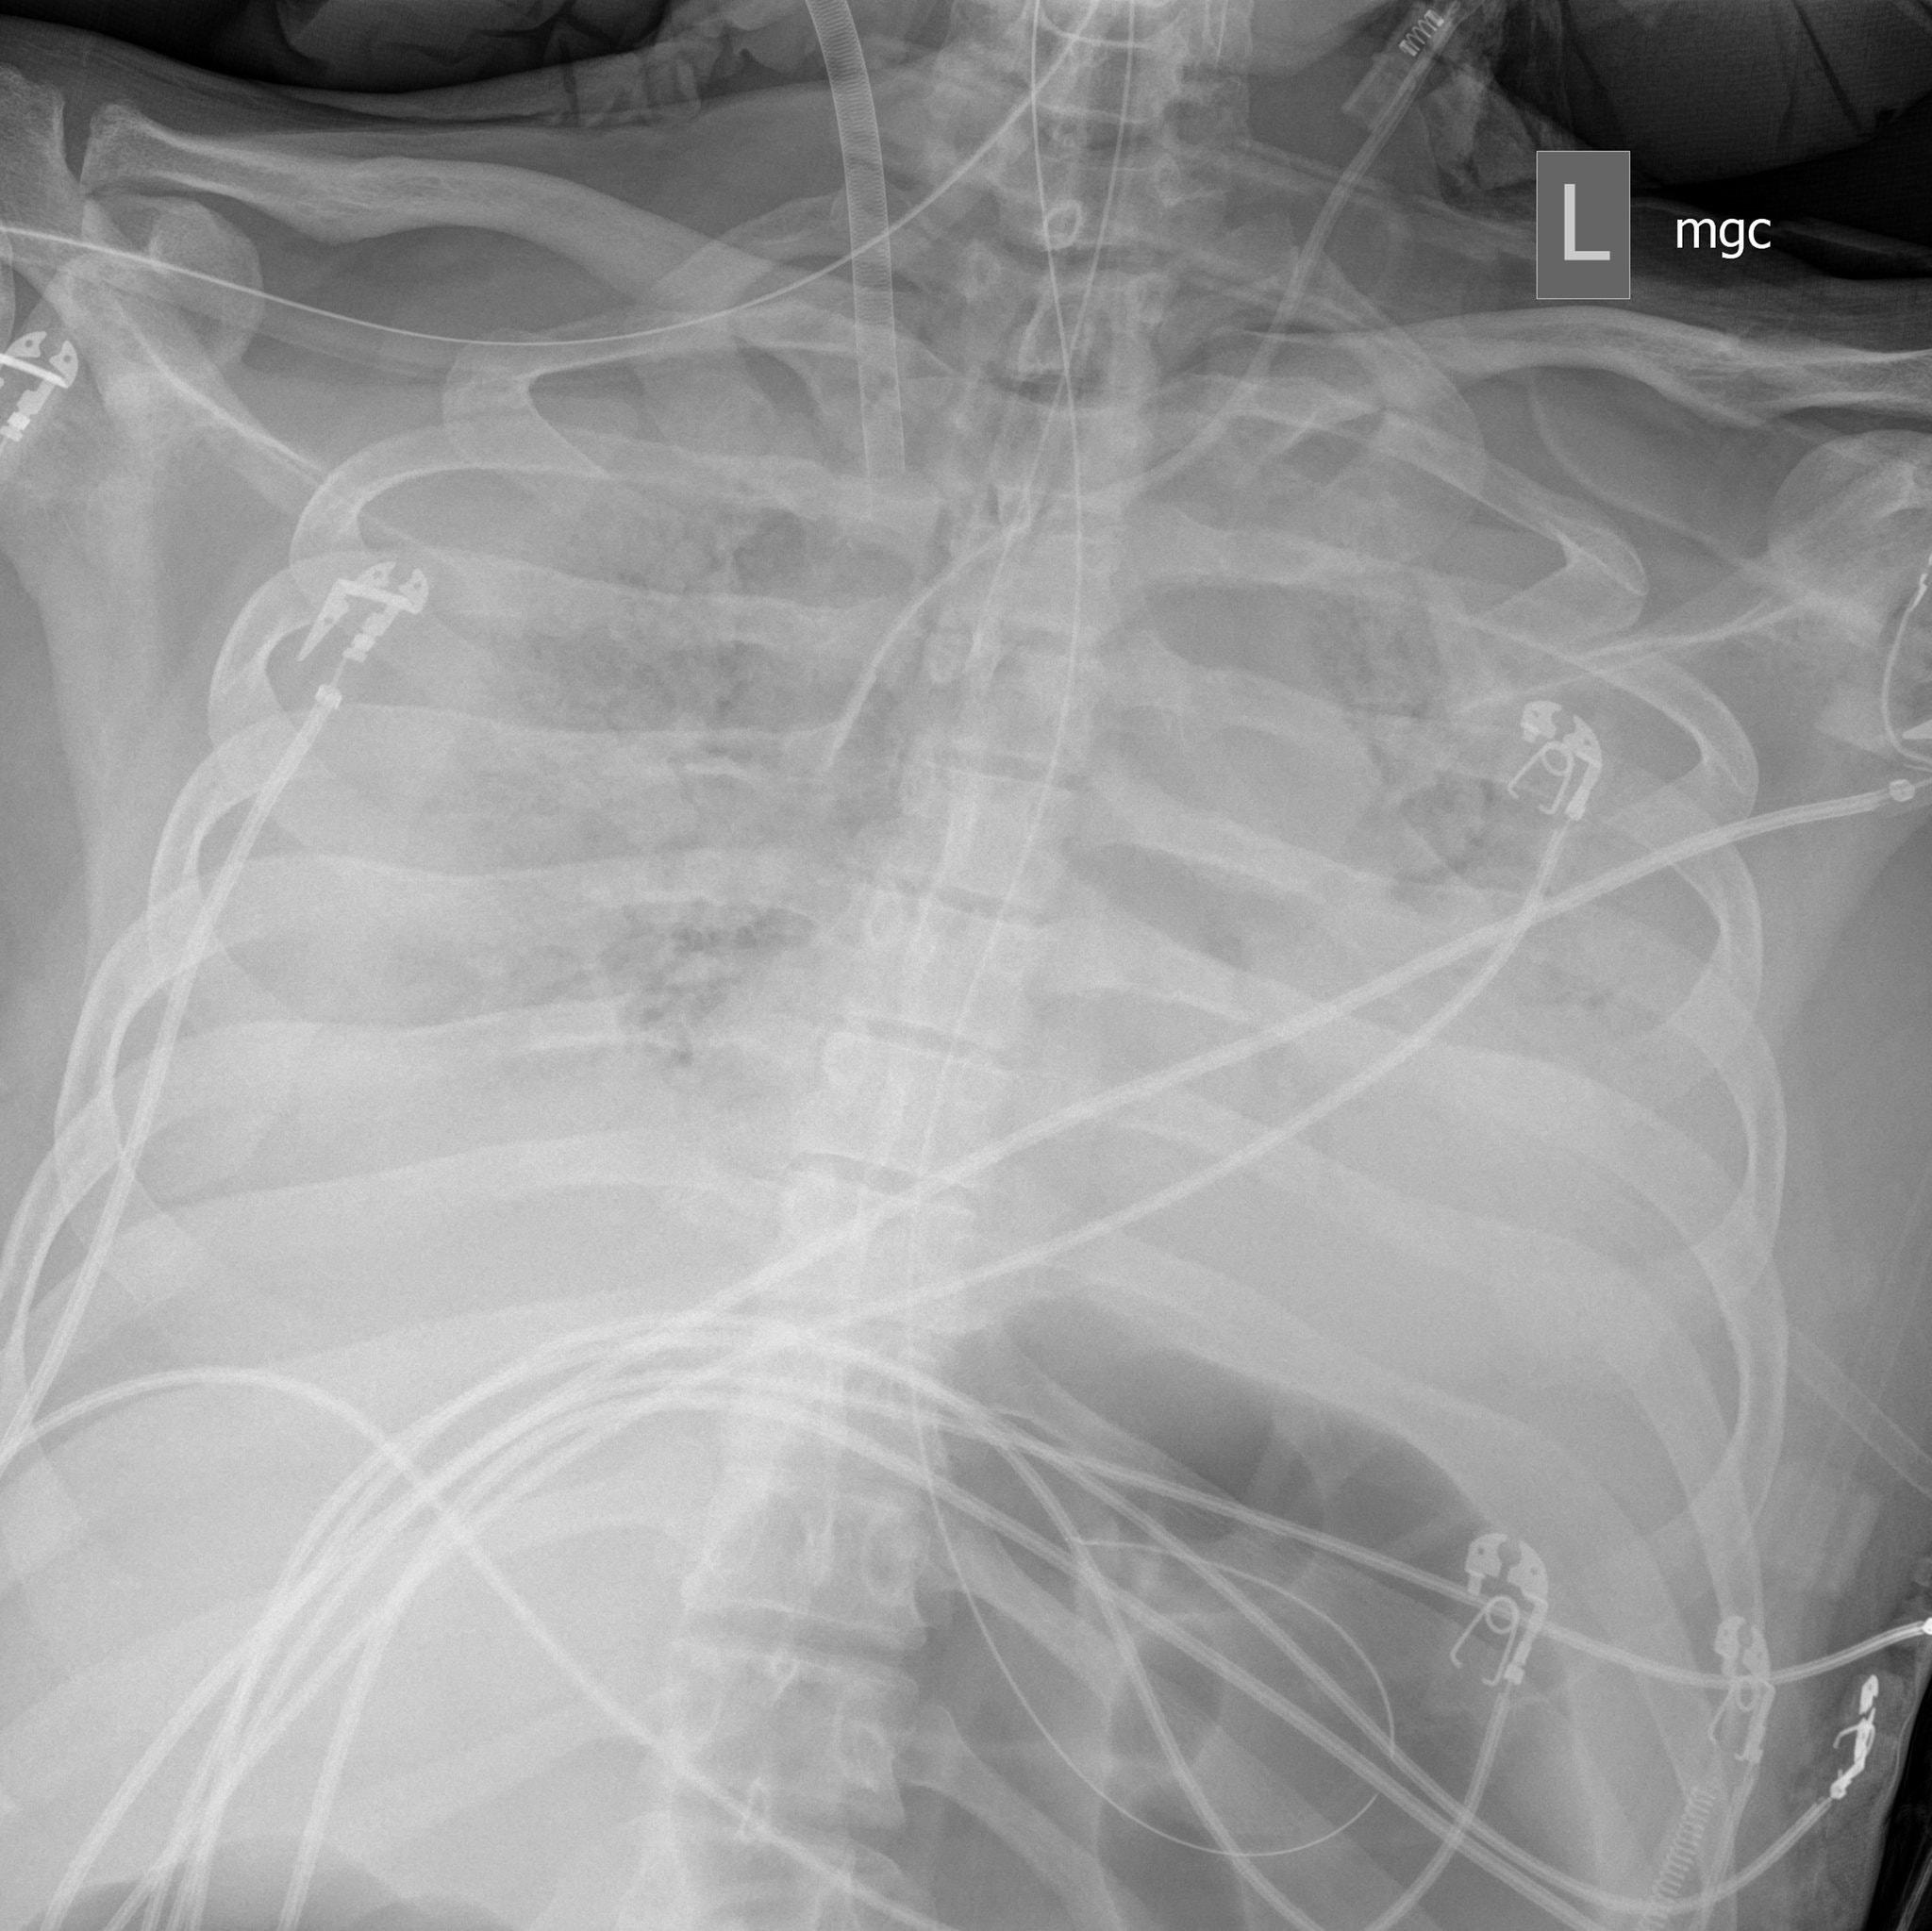

Hình ảnh X-quang phổi của Jim ngày 27/3 tràn ngập màu trắng. Các bác sĩ cho biết đây là một trong những hình ảnh X-quang phổi tệ nhất họ từng thấy. (Ảnh: NYT)

Trong vòng ba ngày sau thủ thuật, hình ảnh chụp X-quang đã cho thấy hy vọng khi một phần nhỏ trong phổi trái của Jim đã hết dịch. Từ sau đó, phổi của Jim bắt đầu được cải thiện từ từ và dần dần tốt hơn đáng kể.